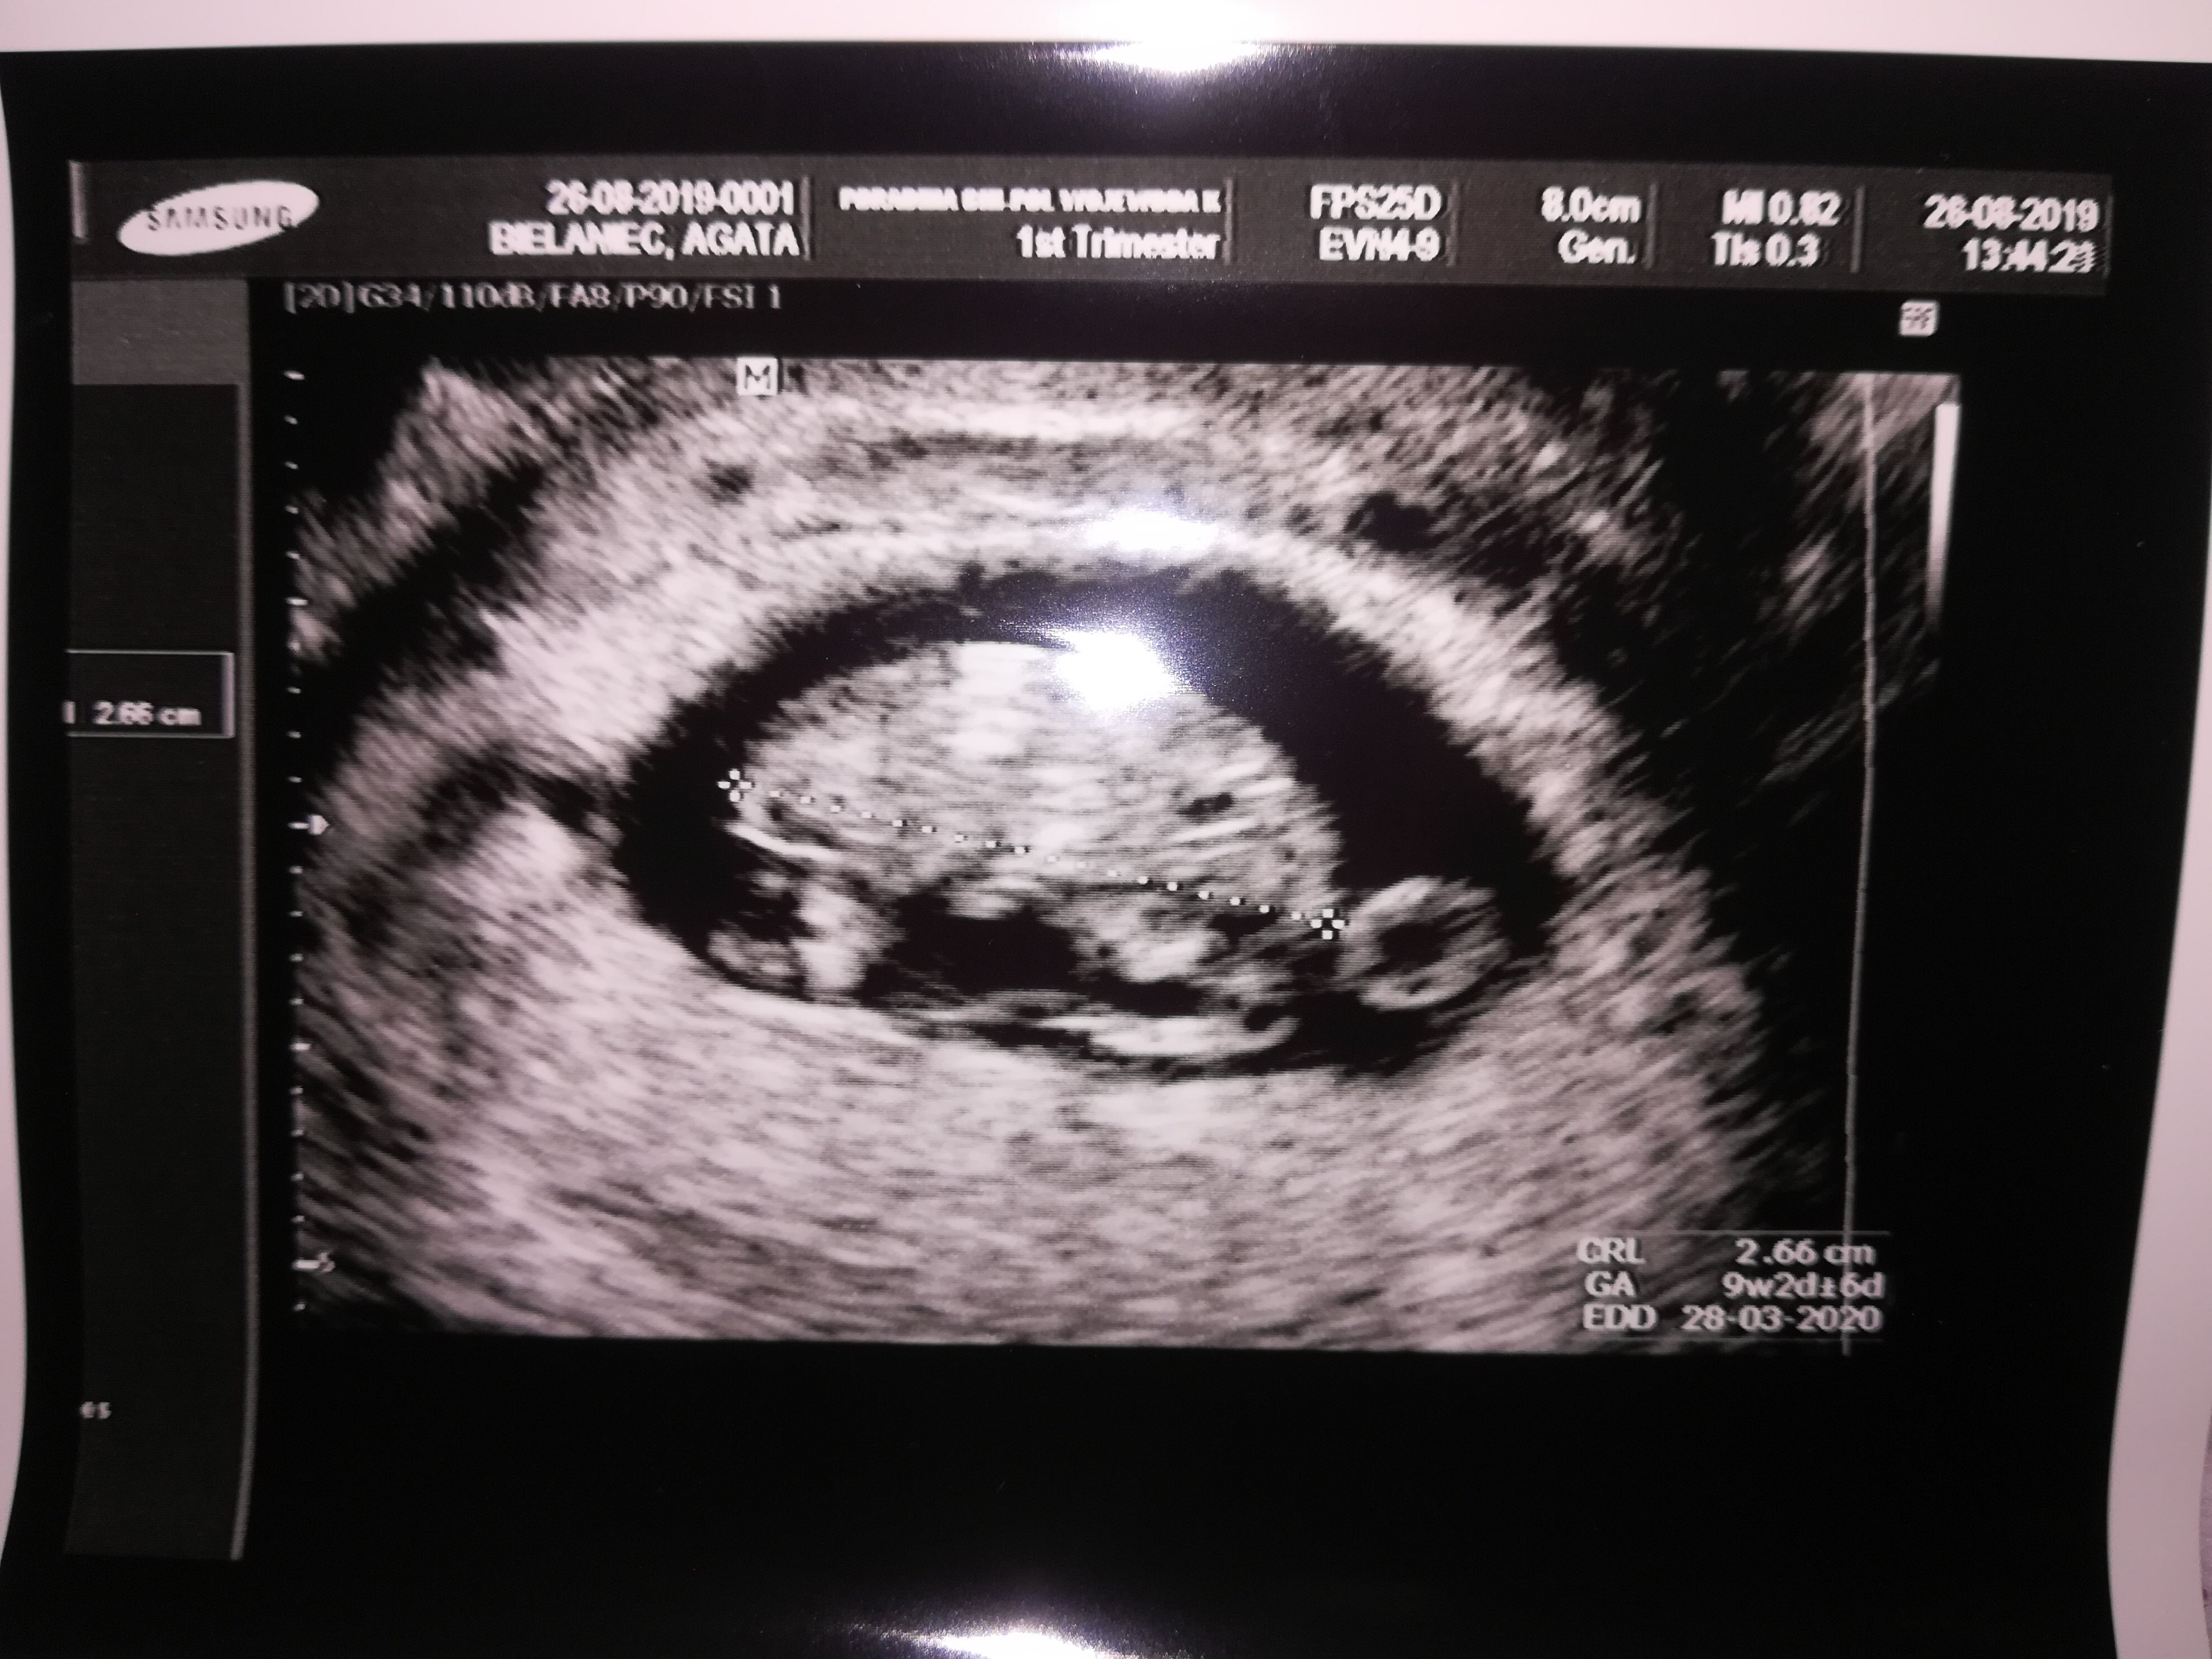

Wy widzicie tak jak ja głowę oczko nosek rączki i nóżki moja rodzina i mój mąż i moja córka do mnie ze to żółwik oni nic nie widzą mówią jakąś plama mama to spanikowala że to takie zniekształcone....